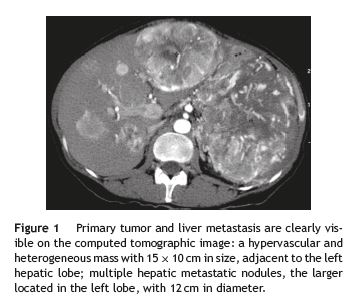

In order to clarify the nature of the abdominal mass and the etiology of the portal hypertension, the patient underwent an abdominal computed tomography (CT) scan, which revealed a large hypervascular pancreatic tumor (Fig. 1), contiguous to the left hepatic lobe, stomach and spleen, as well as multiple hepatic nodules with similar characteristics. It also showed splenic vein thrombosis and exuberant collateral blood vessels around the tumor (Fig. 2). The radiological findings were suggestive of a pancreatic neuroendocrine tumor with liver metastasis, a diagnosis subsequently confirmed by the histological and immunohistochemical studies. The investigation was completed with a chromogranin A analysis (26 nmol/L; reference upper limit 6 nmol/L) and a somatostatin-receptor scintigraphy (OctreoscanTM), which showed no additional secondary locations of the tumor.